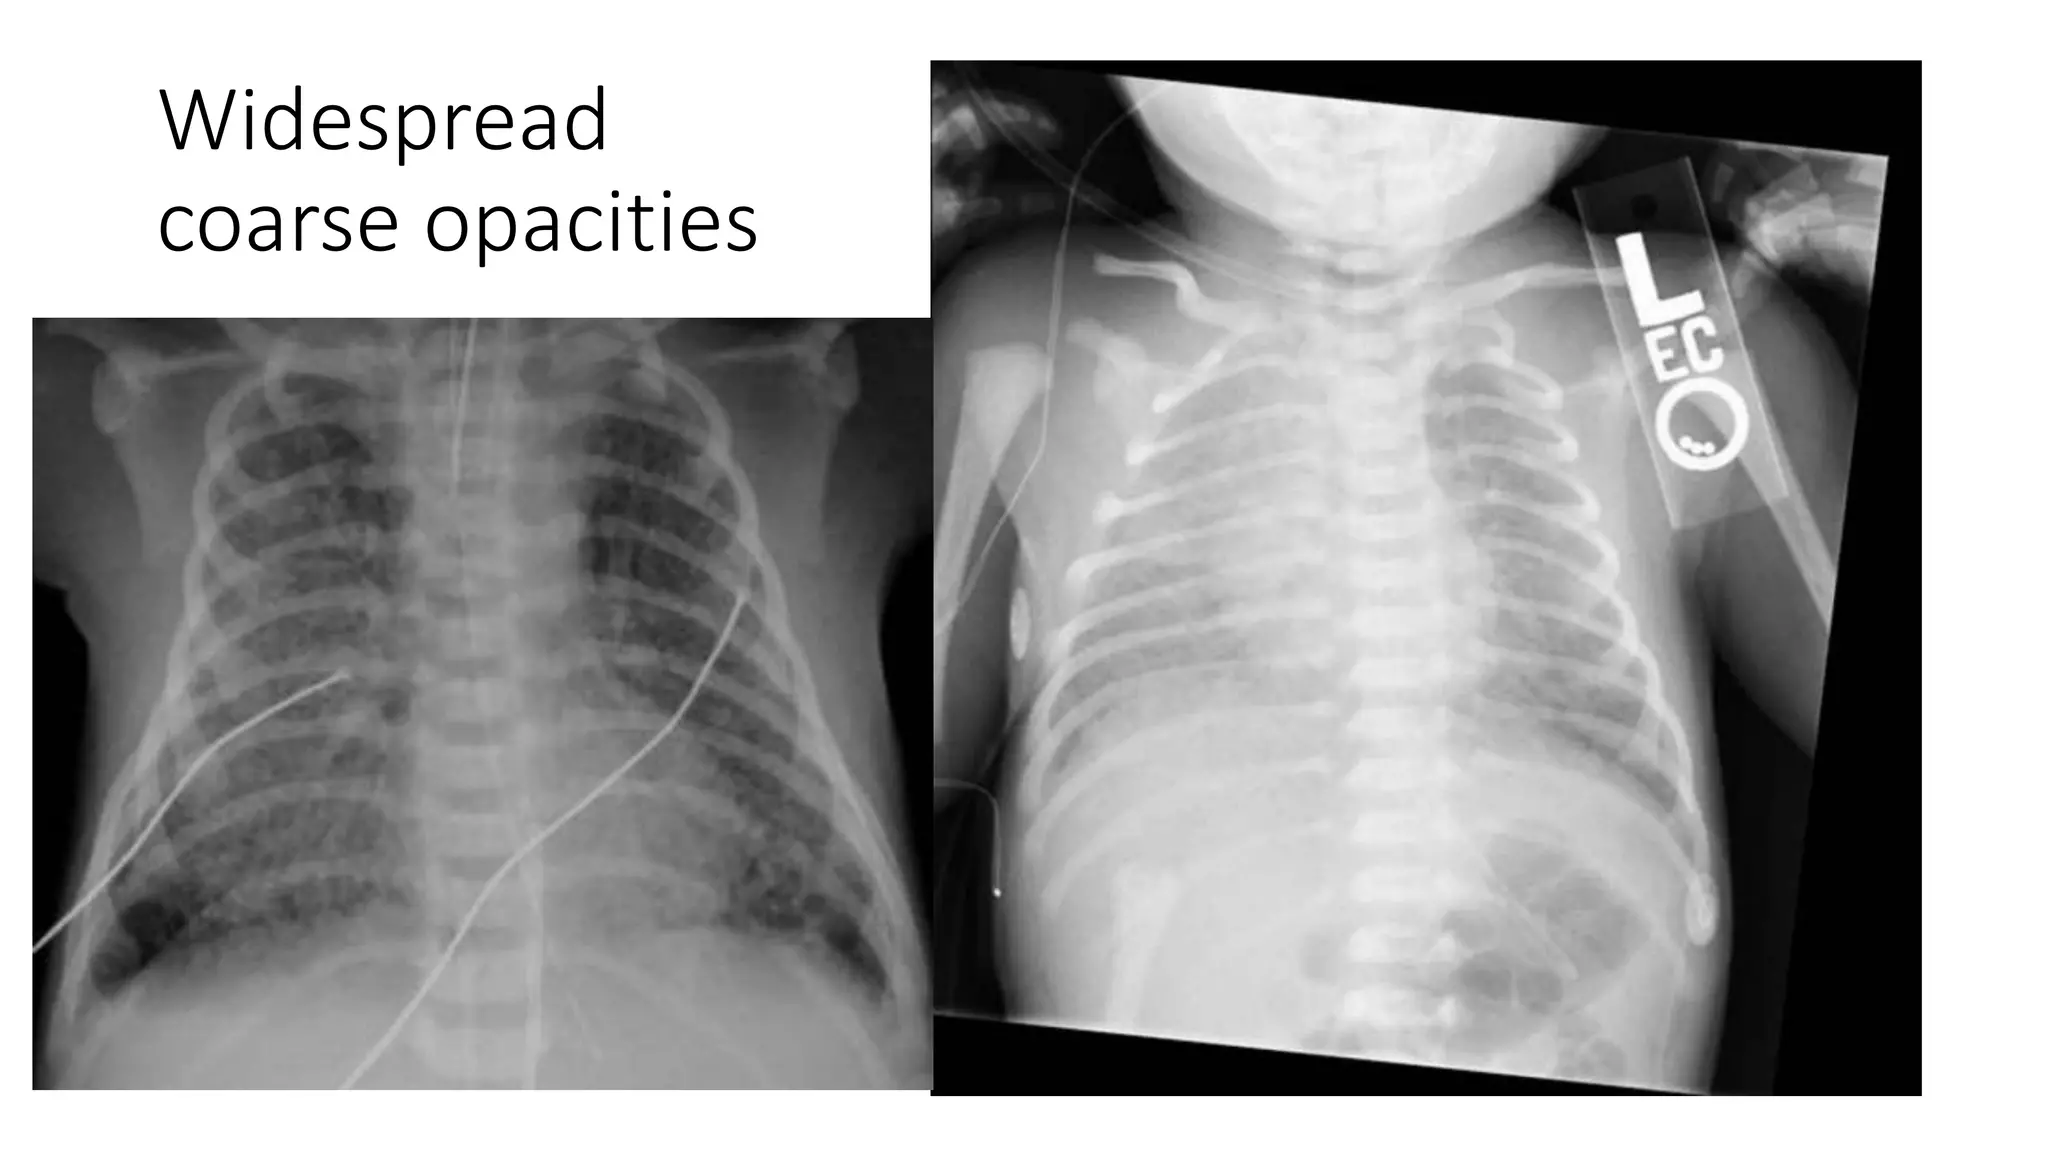

This document provides an overview of neonatal chest x-rays, including when they should and should not be performed, what a normal x-ray looks like, common positions of tubes and catheters, and common causes of respiratory distress in neonates. It discusses the appearance of a normal chest x-ray as well as conditions like respiratory distress syndrome, transient tachypnea of the newborn, meconium aspiration syndrome, and pneumonia. Surgical conditions like diaphragmatic hernia and esophageal atresia are also reviewed.